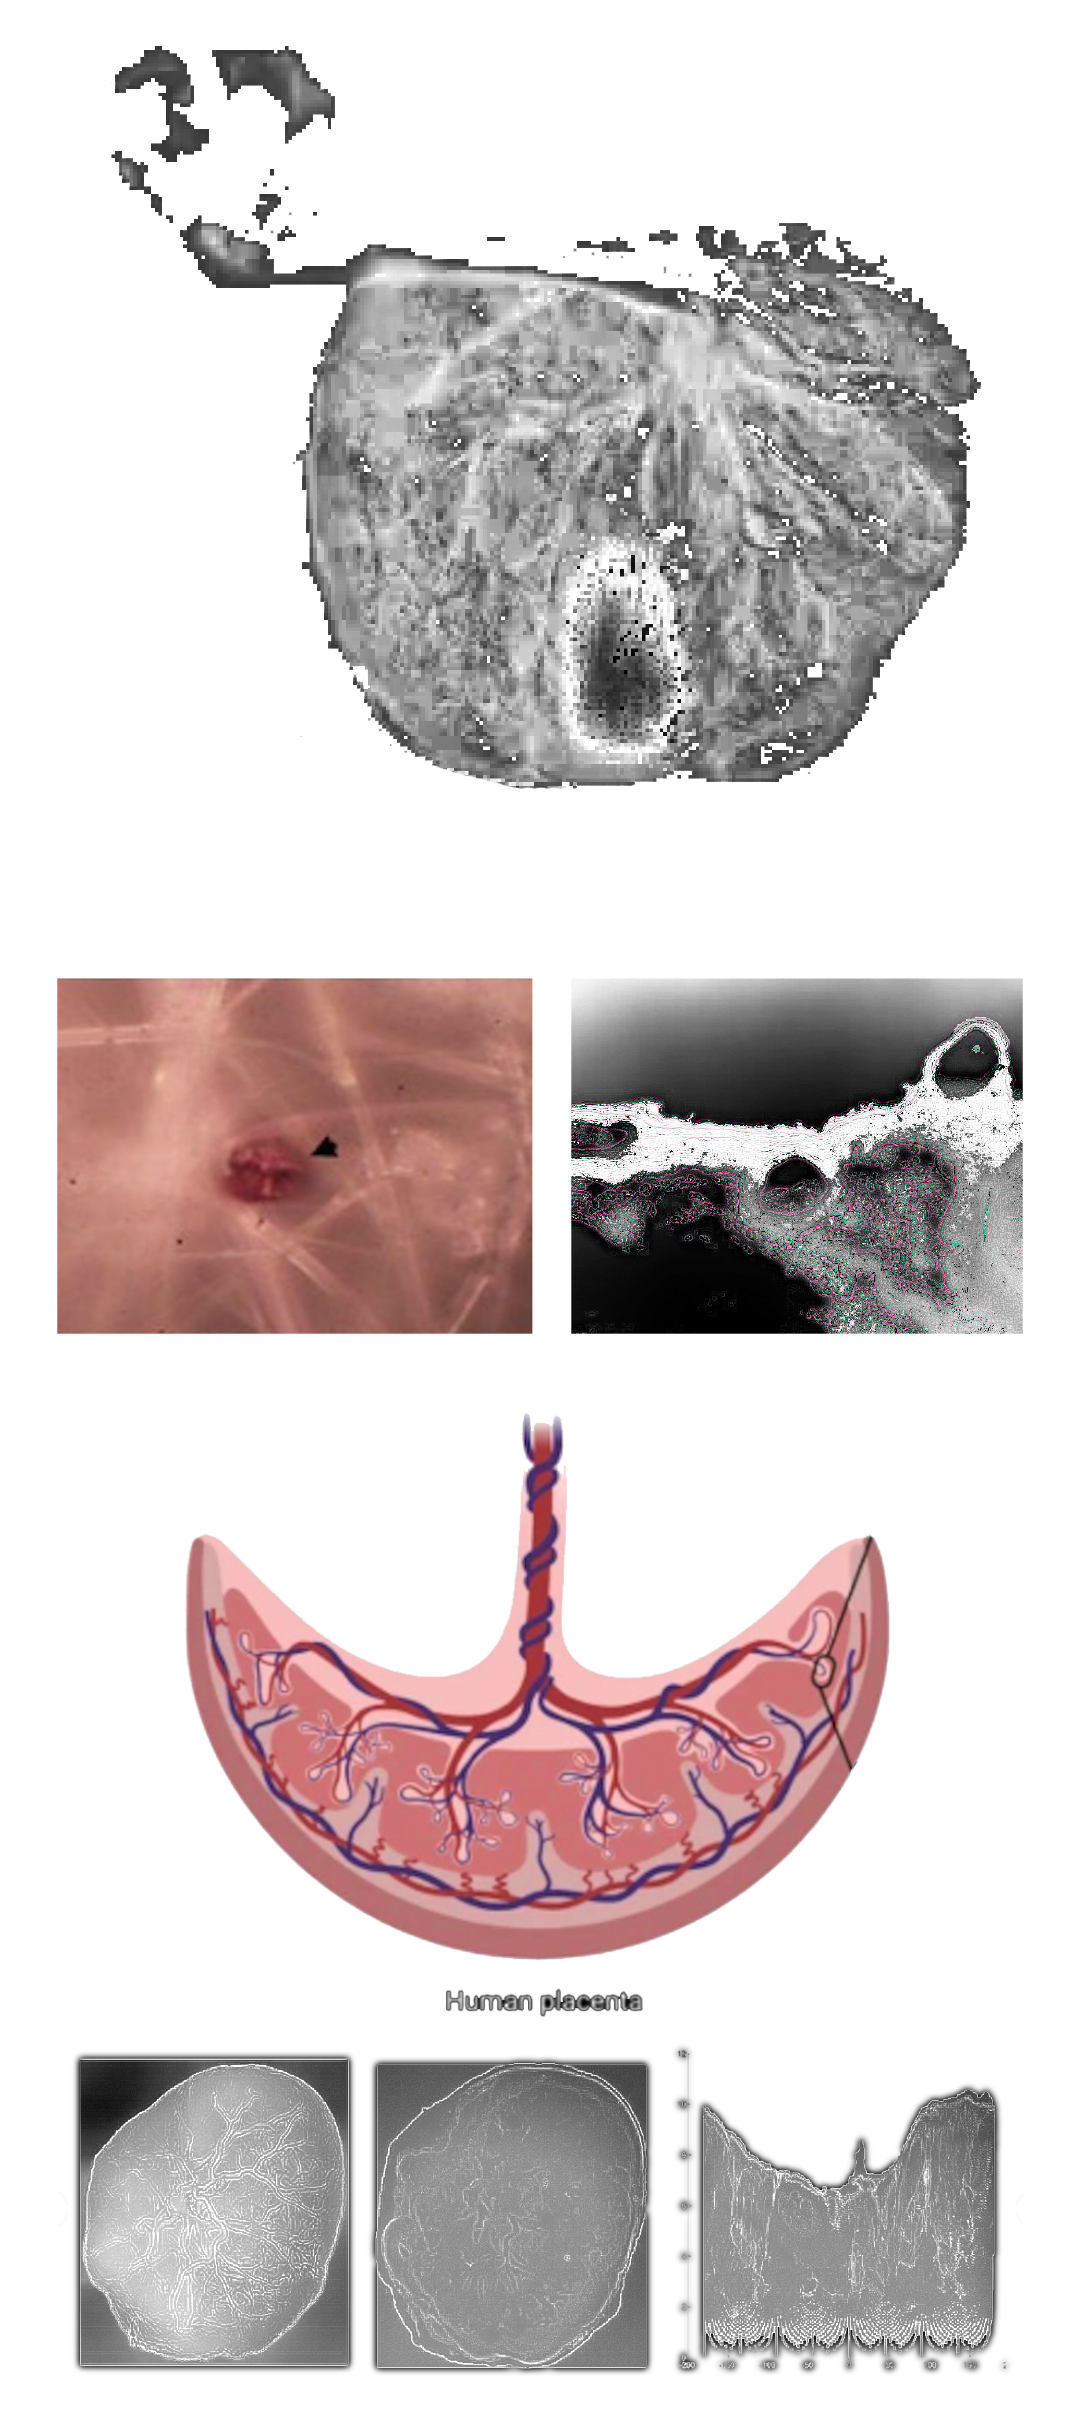

MICROPLASTICS (MPS) ARE DEFINED AS PLASTIC PARTICLES SMALLER THAN 5 MM. THEY HAVE BEEN FOUND ALMOST EVERYWHERE THEY HAVE BEEN SEARCHED FOR AND RECENT DISCOVERIES HAVE ALSO DEMONSTRATED THEIR PRESENCE IN HUMAN PLACENTA, BLOOD, MECONIUM, AND BREASTMILK, BUT THEIR LOCATION AND TOXICITY TO HUMANS HAVE NOT BEEN REPORTED TO DATE. THE AIM OF THIS STUDY WAS TWOFOLD:

1. TO LOCATE MPS WITHIN THE INTRA/EXTRACELLULAR COMPARTMENT IN HUMAN PLACENTA.

2. TO UNDERSTAND WHETHER THEIR PRESENCE AND LOCATION ARE ASSOCIATED WITH POSSIBLE STRUCTURAL CHANGES OF CELL ORGANELLES. USING VARIABLE PRESSURE SCANNING ELECTRON MICROSCOPY AND TRANSMISSION ELECTRON MICROSCOPY, MPS HAVE BEEN LOCALIZED IN TEN HUMAN PLACENTAS. IN THIS STUDY, WE DEMONSTRATED FOR THE FIRST TIME THE PRESENCE AND LOCALIZATION IN THE CELLULAR COMPARTMENT OF FRAGMENTS COMPATIBLE WITH MPS IN THE HUMAN PLACENTA AND WE HYPOTHESIZED A POSSIBLE CORRELATION BETWEEN THEIR PRESENCE AND IMPORTANT ULTRASTRUCTURAL ALTERATIONS OF SOME INTRACYTOPLASMIC ORGANELLES (MITOCHONDRIA AND ENDOPLASMIC RETICULUM). THESE ALTERATIONS HAVE NEVER BEEN REPORTED IN NORMAL HEALTHY TERM PREGNANCIES UNTIL TODAY. THEY COULD BE THE RESULT OF A PROLONGED ATTEMPT TO REMOVE AND DESTROY THE PLASTIC PARTICLES INSIDE THE PLACENTAL TISSUE. THE PRESENCE OF VIRTUALLY INDESTRUCTIBLE PARTICLES IN TERM HUMAN PLACENTA COULD CONTRIBUTE TO THE ACTIVATION OF PATHOLOGICAL TRAITS, SUCH AS OXIDATIVE STRESS, APOPTOSIS, AND INFLAMMATION, CHARACTERISTIC OF METABOLIC DISORDERS UNDERLYING OBESITY, DIABETES, AND METABOLIC SYNDROME AND PARTIALLY ACCOUNTING FOR THE RECENT EPIDEMIC OF NON-COMMUNICABLE DISEASES.